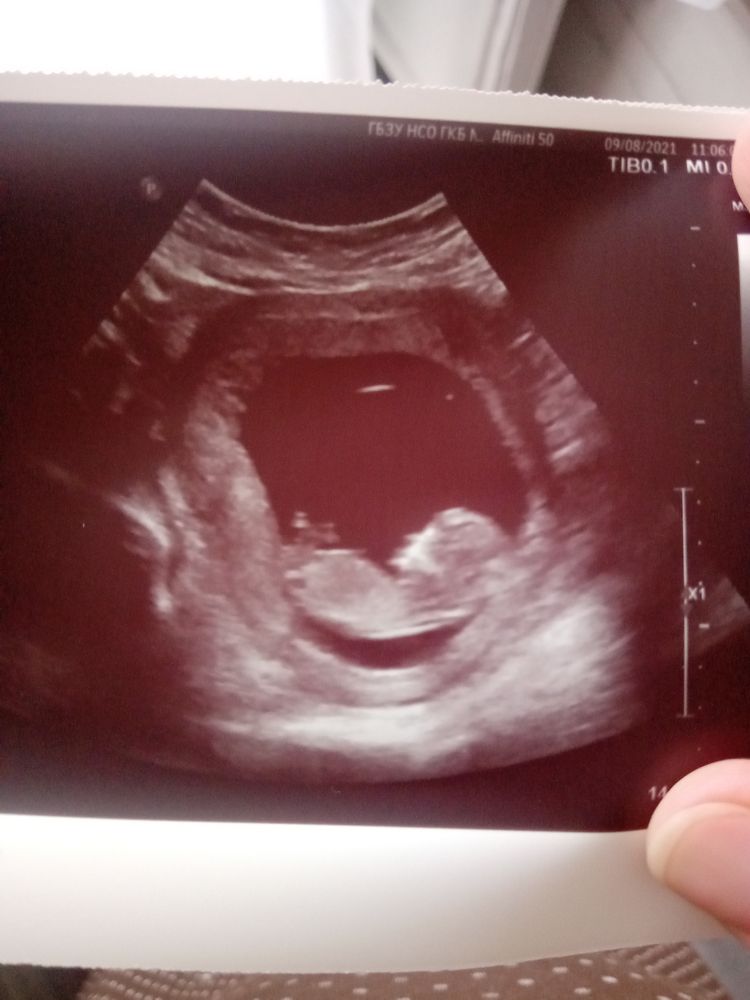

Прибавка веса +3,1 от добеременного.Ну и покажу малышку от начала до 20-й недели)))))